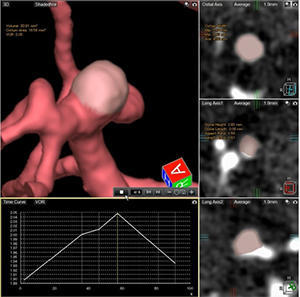

1.4D脳動脈形態計測

未破裂動脈瘤の治療を行う術前評価として,動脈瘤形状を自動で計測し各種パラメータを算出することで,治療選択のサポートを行える。さらに従来は目視に頼っていた動態の評価から,連続して収集した各情報から位相ごとに色を付けて重ね合わせることができ,ブレブの拍動部位の色分けや計測が行えるため,どのように変化しているか評価が可能となり,未破裂動脈瘤の破裂リスクの予測など期待できる。